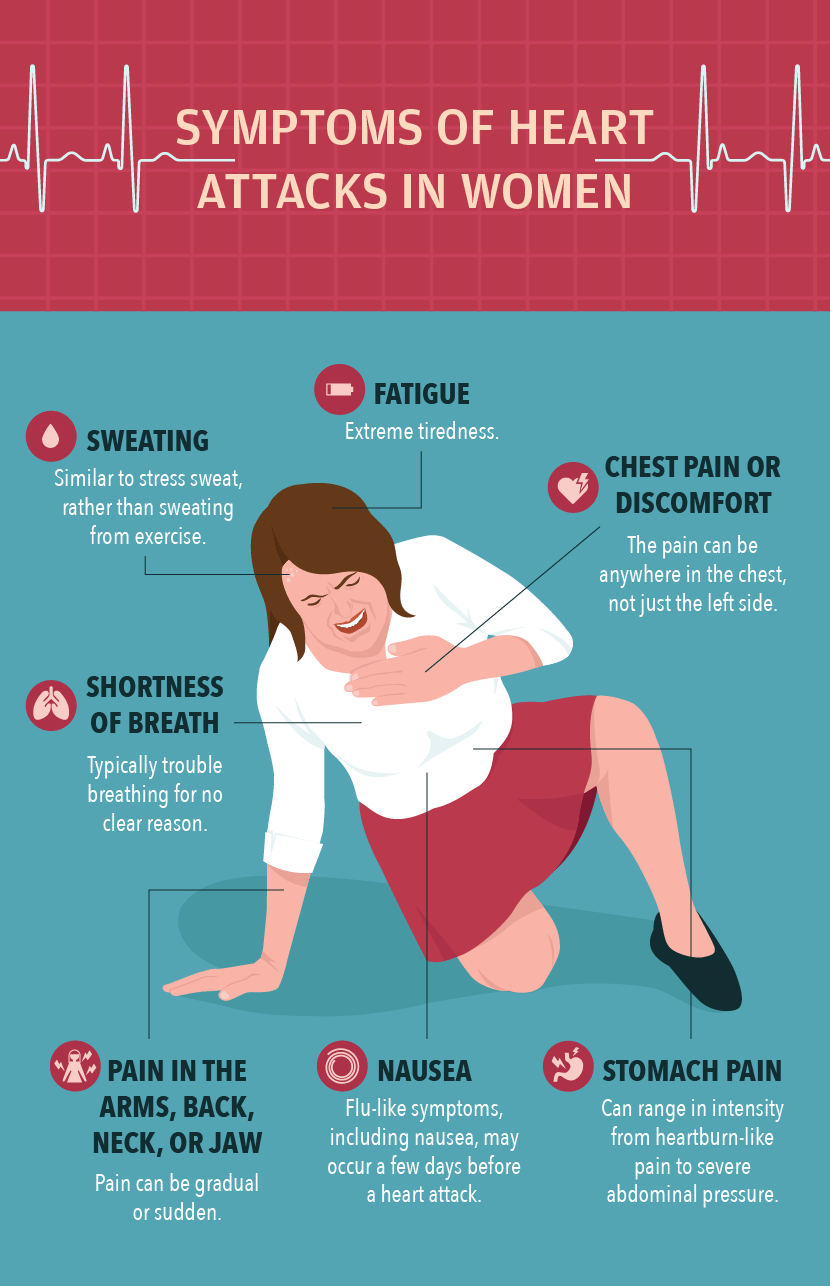

Η εκπαίδευση των γυναικών σχετικά με τους παράγοντες κινδύνου που σχετίζονται με την καρδιακή ανεπάρκεια μπορεί να τις βοηθήσει να υιοθετήσουν υγιείς πρακτικές και άλλα προληπτικά μέτρα εγκαίρως πριν από την εμφάνιση καρδιακής προσβολής.

Δεν είναι ξεκάθαρο γιατί ο κίνδυνος των γυναικών είναι μεγαλύτερος, αλλά οι ερευνητές υποπτεύονται ότι μπορεί να συμβαίνει επειδή οι γυναίκες είναι λιγότερο πιθανό να επισκέπτονται τακτικά καρδιολόγους και να έχουν χαμηλότερα ποσοστά λήψης καρδιακών φαρμάκων.

Επιπλέον, οι μελέτες σχετικά με τις καρδιακές προσβολές έχουν ιστορικά στραφεί προς τους άνδρες και απαιτείται περισσότερη έρευνα για τον προσδιορισμό των κλινικών διαφορών στις καρδιακές προσβολές στους άνδρες έναντι των γυναικών για να καλυφθεί το κενό θνησιμότητας.